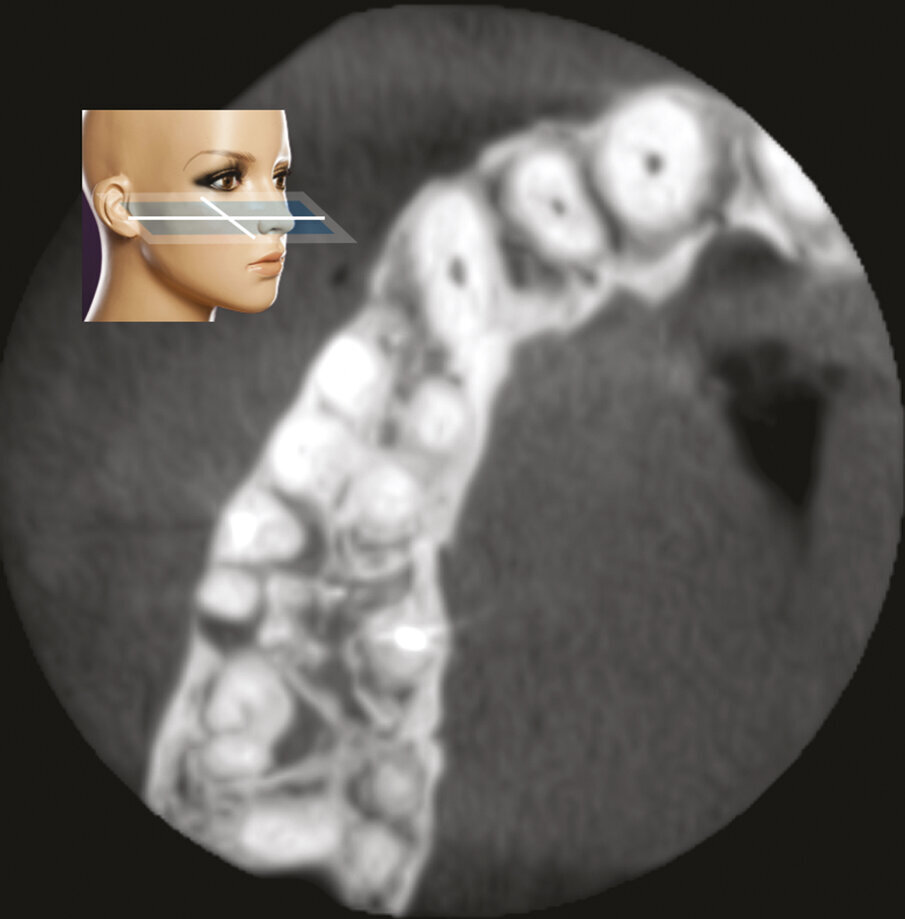

Fig. 2a - Radiografia preoperatoria del secondo molare superiore di sinistra. La paziente lamenta dolore alla masticazione su questo dente, trattato endodonticamente pochi mesi prima. La stessa viene indirizzata con la specifica richiesta di eseguire la terapia chirurgica e di non aprire una cavità d’accesso, allo scopo di non sciupare la “nuova” corona ceramica da poco cementata.

Fig. 2b - Una piccola lesione è evidente all’apice della radice mesiovestibolare.

Fig. 2c - La CBCT mostra l’inclinazione distale della radice distovestibolare del primo molare.

Fig. 2d - La sezione coronale mette in evidenza il fatto che la radice distovestibolare del primo molare è vestibolare alla radice mesiovestibolare del secondo molare.

Fig. 2e - Le quattro sezioni assiali mostrano come la radice distovestibolare del primo molare sia vestibolare rispetto alla radice mesiovestibolare del secondo molare. Questa particolare situazione anatomica rappresenta una ovvia controindicazione all’approccio chirurgico.